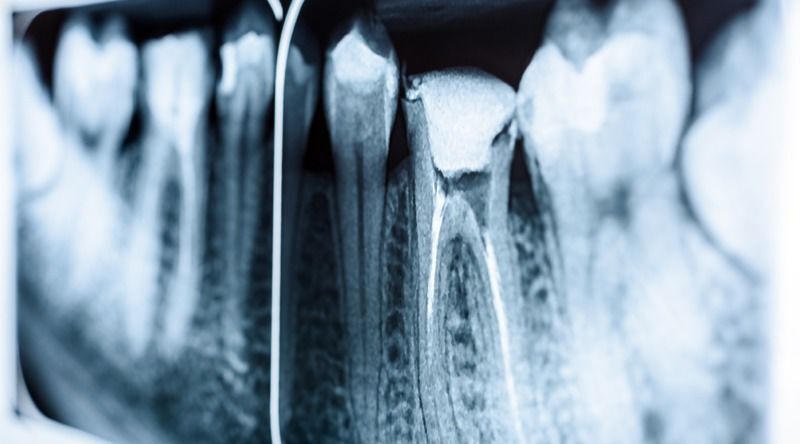

Con todos estos datos en mente, Adam Celiz y sus colegas de especialistas en biomateriales terapéuticos de la Universidad de Nottingham han intentado buscar un buen sustituto a las técnicas actuales de endodoncia donde se quita la pulpa del diente y el tejido blando (el cual contiene vasos sanguíneos, nervios y otros tejidos), un tratamiento que acaba debilitando la base del diente y que, en ocasiones, implica que la pieza dentaria necesite ser retirada.

Su método consiste en el uso de un biomaterial sintético que estimula el crecimiento de las células madre en la pulpa del diente. De la misma forma que los biomateriales usados actualmente tan solo como relleno, este material basado en células madre también se inyecta directamente en el diente y se endurece con luz ultravioleta.

En las pruebas in vitro de laboratorio, este biomaterial de células madre ha conseguido estimular la proliferación y diferenciación de dichas células en la dentina, el tejido óseo que forma la mayor parte del diente justo por debajo del esmalte blanco. Según los investigadores, usando este tipo de relleno en un diente dañado se podría reparar el diente sin acabar debilitándolo o incluso sustituyéndolo por un implante dental como sucede hoy en día.